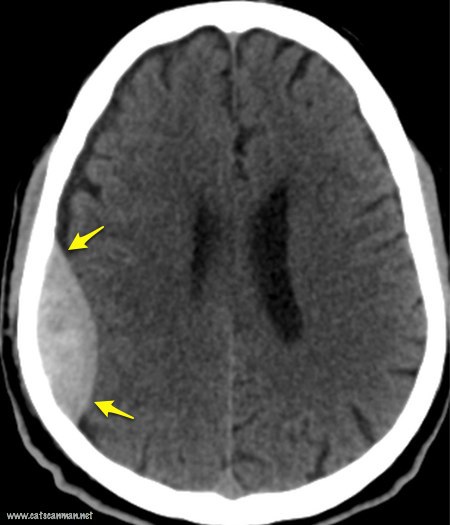

Отличие субдуральной и эпидуральной гематом головного мозга

Эпидуральная гематома (в "форме лимона")

Судбуральная гематома (в "форме банана")